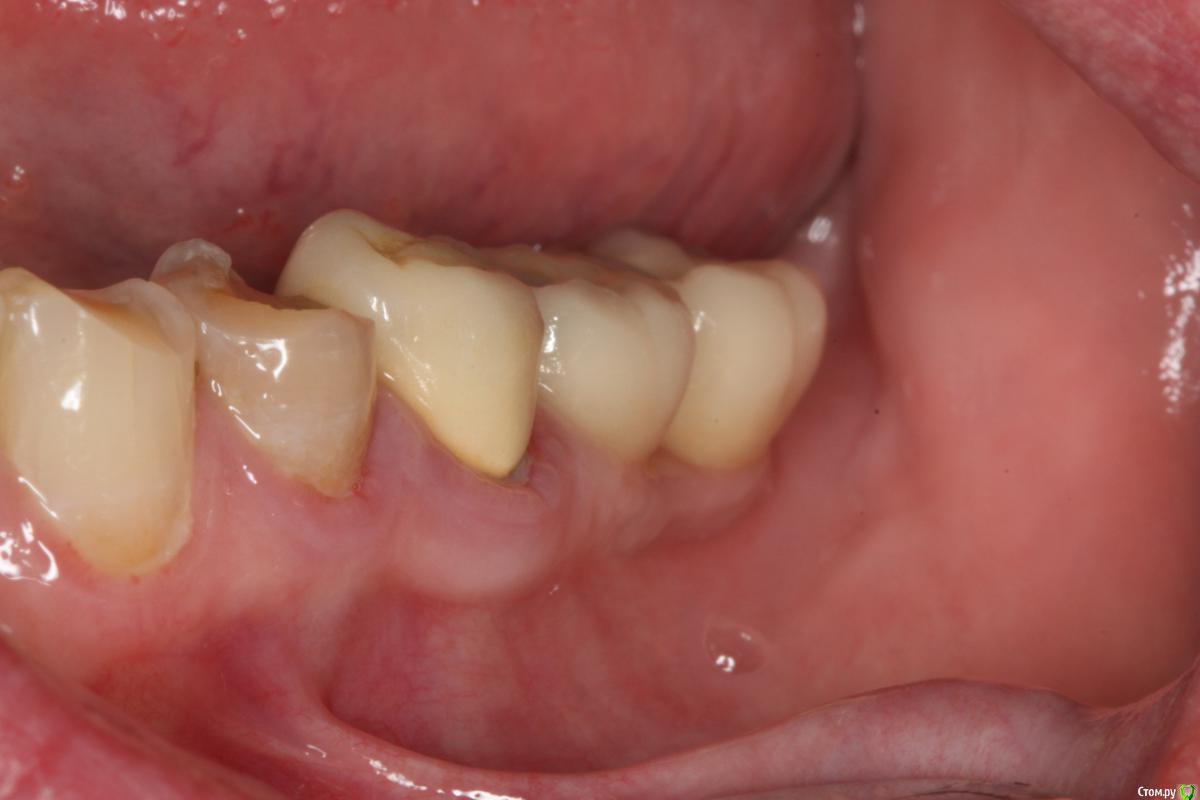

Pavel-Pskov Опубликовано 24 мая, 2016 Поделиться Опубликовано 24 мая, 2016 В момент снятия слепков май 2014 г.Неделя назад Ссылка на комментарий